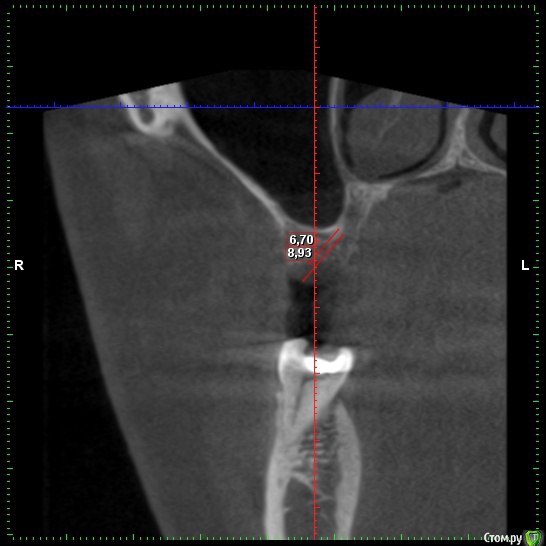

zubovolok Опубликовано 8 октября, 2018 Поделиться Опубликовано 8 октября, 2018 (изменено) Коллеги сомневаюсь по поводу высоты кости, какое измерение правильное? Изменено 8 октября, 2018 пользователем zubovolok Ссылка на комментарий

АнтонТЛТ Опубликовано 8 октября, 2018 Поделиться Опубликовано 8 октября, 2018 5.41мм правильный замер. Зубы могут быть устойчивыми и при меньшем объеме костной ткани вокруг. 2 Ссылка на комментарий